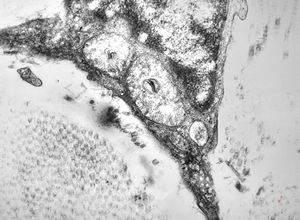

F, 46y. | verruca vulgaris … intranuclear virions